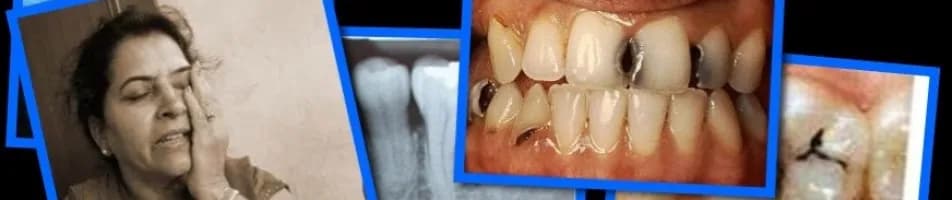

Po wyrwaniu zęba ważne jest, aby odpowiednio zadbać o miejsce ekstrakcji, aby złagodzić ból i wspomóc proces gojenia. Istnieje kilka preparatów, które mogą być stosowane miejscowo, aby zmniejszyć dyskomfort oraz zapobiec infekcjom. Wśród nich znajdują się Baikadent, Sachol i Elugel, które mają różne właściwości i zastosowania.